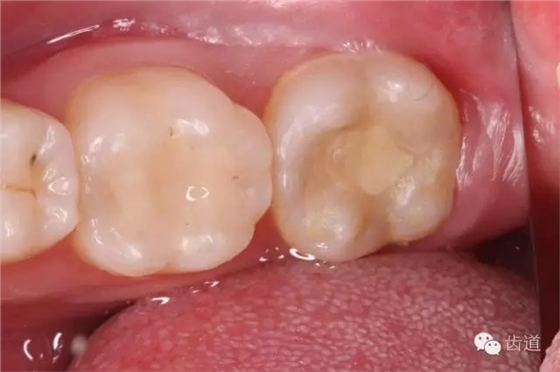

一診(2015.01.25): 主訴:左下后牙咬食疼痛約2天 既往史:無特殊 3年前因左下后牙蟲牙不適,已在外院治療,治療后癥狀消失,約2天前,左下后牙開始出現(xiàn)咬合時(shí)劇烈疼痛,無冷熱刺激痛,無夜間痛,否認(rèn)咀嚼硬物史,約1天前,開始出現(xiàn)自發(fā)性跳痛,咬合可適當(dāng)緩解疼痛,未自行服用藥物,未在外院治療,癥狀持續(xù)為緩解,遂于我院就診。 口外檢查:面部對(duì)稱,無腫脹 口內(nèi)檢查: 36合面樹脂樣材料充填,邊緣密合,牙體及修復(fù)材料表面均未見明顯缺損及裂紋,未探及繼發(fā)齲,探痛-,叩痛-,松動(dòng)-,冷水刺激痛-,未探及牙周袋及附著喪失,牙齦無紅腫,電活力測(cè)試平均值為15;37合面樹脂樣材料充填,邊緣密合,牙體及修復(fù)材料表面均未見明顯裂紋,未探及繼發(fā)齲,探痛-,叩痛+++,松動(dòng)-,冷水刺激痛-,未探及牙周袋及附著喪失,牙齦無紅腫,電活力測(cè)試無反應(yīng);38埋伏阻生,可探及齦下牙冠,探痛-,牙齦無紅腫。 26、27牙體未見明顯充填物、缺損、齲壞及裂紋,探痛-,叩痛-,松動(dòng)-,冷水刺激痛-,未探及牙周袋及附著喪失,牙齦無紅腫; 影像學(xué)檢查: 全景片及X線根尖片顯示36合面充填物影像,靠近髓腔,未見根折影像,未見牙槽骨吸收,未見根分叉透射影,未見根尖周暗影;37合面充填物影像,靠近髓腔,未見根折影像,未見牙槽骨吸收,未見根分叉透射影,根管影像清晰,根中上三分之二粗大,根尖三分一分為近遠(yuǎn)中兩根管,形態(tài)均呈弧形,根尖周膜連續(xù)性中斷,根尖周透射影明顯,進(jìn)一步測(cè)量顯示:髓室頂最低點(diǎn)到髓底的距離a,與髓室頂最低點(diǎn)到根尖孔的距離b,兩者關(guān)系為a/b>0.2;38近中阻生,牙根尚未發(fā)育完全,未見冠周明顯透射影像;。CBCT片顯示:在水平斷層上,可見37根管在根尖三分之一為彎曲偏向頰側(cè)的C型,存在近遠(yuǎn)中兩個(gè)主根管,中間峽部相連;在矢狀斷層上,可見37根管遠(yuǎn)中根尖孔擴(kuò)大,遠(yuǎn)中根尖狹窄處位于離解剖根尖約1mm處 37慢性根尖周炎急性發(fā)作(牛牙癥) 37擬行根管治療+嵌體間接修復(fù)或根管治療+直接樹脂充填,告知患者嵌體間接修復(fù)及樹脂直接充填兩種方法的優(yōu)缺點(diǎn)、診療過程及費(fèi)用,患者知情,同意選擇根管治療+嵌體間接修復(fù)方案,簽署術(shù)前知情同意書。 37無局部麻醉下,橡皮障放置,涂布邊緣封閉劑,顯微鏡下,合面開髓,死髓,無惡臭,無滲出液,Endo-Z開髓鉆揭全髓頂,探及髓腔內(nèi)壞死牙髓組織,3%次氯酸鈉浸泡髓腔5min,超聲清理髓腔,顯微鏡下探及近遠(yuǎn)中主根管,及根管間峽部。通過放入初尖銼及電子根管根管長度測(cè)量儀確定根管長度為18mm,利用手用K銼將根管預(yù)備至15#,再利用Waveone 25#預(yù)備根管至工作長度,之后,10ml 3%次氯酸鈉沖洗根管,超聲無菌水蕩洗,選取25#06錐度牙膠為主牙膠,拍攝示尖片,顯示到達(dá)根管長度。然后,17% EDTA凝膠處理根管壁,5ml 2%氯己定溶液完成終末沖洗,螺旋輸送器導(dǎo)入氫氧化鈣,放置棉球1,ZOE暫封。